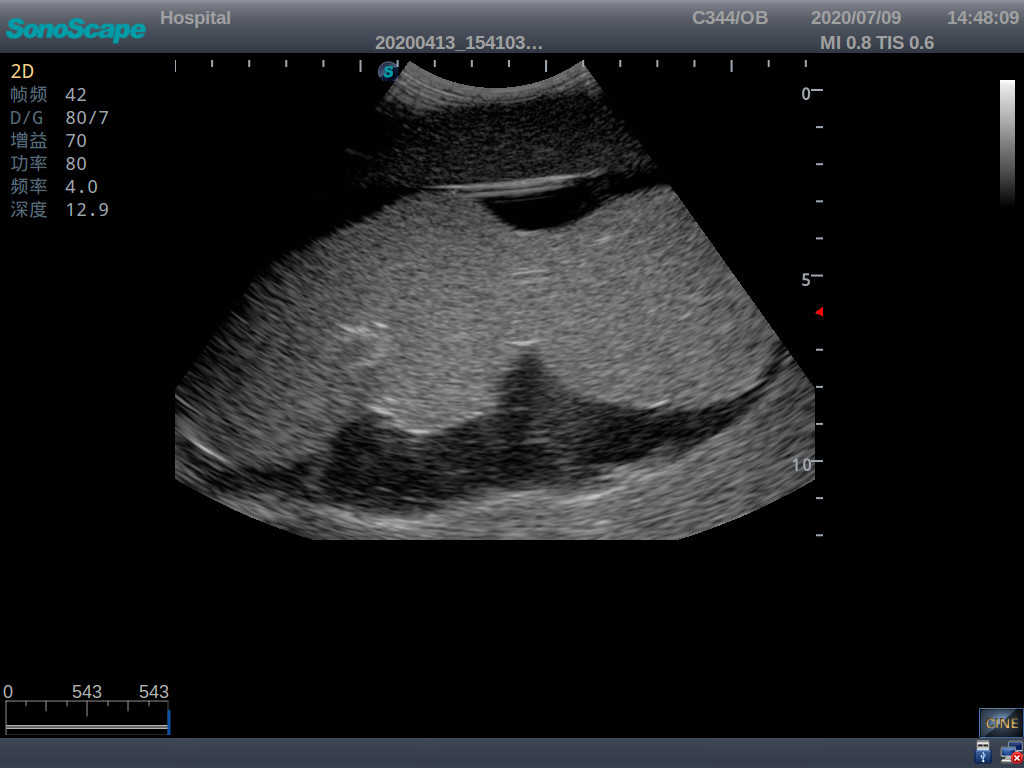

· High-quality ultrasound images for users to recognize 22-week fetus, placenta, placenta, umbilical cord and amniotic fluid

· Compatible with various real ultrasound machines